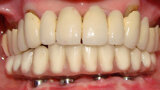

Fig. 4 Prótesis Híbrida inmediata y radiografía control con 6 años post-operatorio